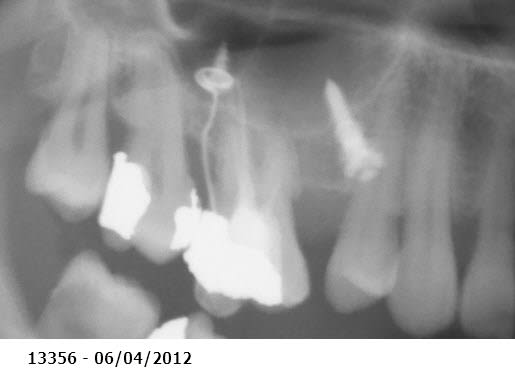

Patiente moins de 40 ans, qui a un peu laissé trainer les choses et désire s'en occuper maintenant. Elle pensait avoir droit aux complets mais je lui ai tout de suite dit "mais nooooooooon !". Possibilités financières limitées (pas d'implanto).

Les égressions dues au manque de calage postérieur sont ici extrêmes. La dévitalisation + élongation coronaire + couronnes ou bridges plus ou moins dans la courbe de Spee des molaires maxillaires, risque de me faire atteindre les furcations.

La seule solution viable est chirurgicale et implantaire car en plus les molaires sup ont déjà une grosse perte osseuse (furcation sur la 27 ? - parodontite chronique ?) donc pas de plastie osseuse possible en conservant les dents postérieures.

les papilles n'ont pas l'air au mieux de leur forme